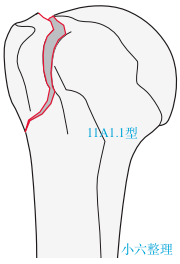

11 C 型:关节内,四部分骨折(解剖颈)。